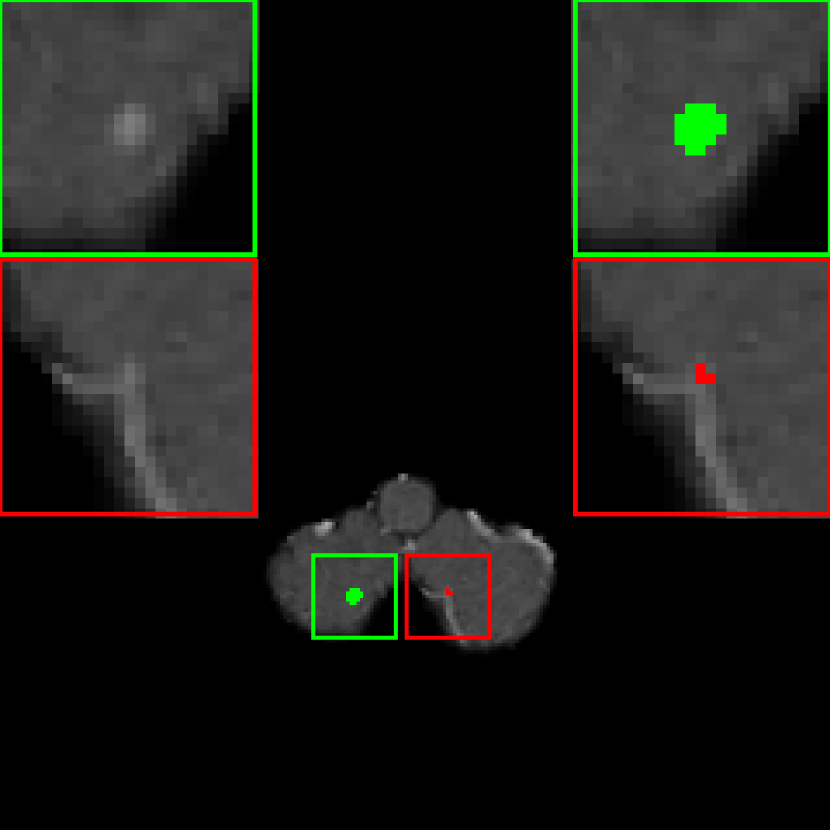

Figure 2: Exemplary images acquired from different time points: (a) temporal prior image; (b) current main image, where the contour indicated by the arrow is segmented incorrectly as a metastasis by a neural network that used the prior image as an additional channel as opposed to an additional pathway; (c) difference between (a) and (b), where the bright region indicated by the arrow is the main cause for the incorrect segmentation.

In contrast-enhanced MRI images with 3D volumetric gradient echo imaging (e.g., BRAVO, GE Healthcare; MPRAGE, Siemens Healthcare; 3D TFE; Philips Healthcare) 36, many structures such as blood vessels are also enhanced by contrast agents. Hence, they have similar appearance to metastases in the regard to intensity, shape, and size in 2D intersectional planes. As a consequence, it is very challenging for human experts to distinguish them. BM differ from blood vessels in several aspects. One is that although they appear similar in 2D intersectional planes, they have distinct morphological appearance in 3D space. For example, enhanced vascular structures are tube-like structures with bifurcations, while the majority of BM are sphere-like structures 37. Therefore, 3D neural networks are advantageous over 2D networks to extract 3D features. In addition, BM have relatively larger morphological changes over time than normal tissues. Without treatment BM volume size typically grows faster than normal tissues due to the high proliferation rate of tumor cells. With treatment BM volume sizes change depending on treatment response, for example, volume size decreases in regression, increases in progression, and oscillates (increases first and later decreases) in pseudo-progression 38. In radiation therapy, patients have regular follow-up MRI scans in approximately every 4-6 weeks. Therefore, by comparing two images acquired from two time points, if a high contrast structure emerges or grows, this structure has high confidence to be a metastasis. To integrate such temporal prior information in deep learning, two potential ways are possible: using the temporal prior volume as an additional input channel or as an additional input path. As anatomical structures imaged at different time points cannot be perfectly registered to the same position, using temporal prior volumes as an additional channel will result in a high FP rate. An example is displayed in Fig. 2, where a normal tissue region indicated by the arrow in Fig. 2(b) is segmented incorrectly as a metastasis. Such mis-segmentation is mainly caused by the imperfect registration, since high intensity difference is observed in the corresponding region of the difference image (Fig. 2(c)). To avoid such problem, in this work we propose to put the temporal prior volume as an additional input path, where features from two time points are merged at deep layers. For distinction, the modified DeepMedic architecture is called DeepMedic+ in this work. The overall DeepMedic+ architecture is displayed in Fig. 3, where the normal resolution subvolumes from both the prior and main datasets as well as two low resolution subvolumes from the main dataset are fed into DeepMedic+. Note that for volumes without any temporal prior, an empty prior volume with zero values is used.